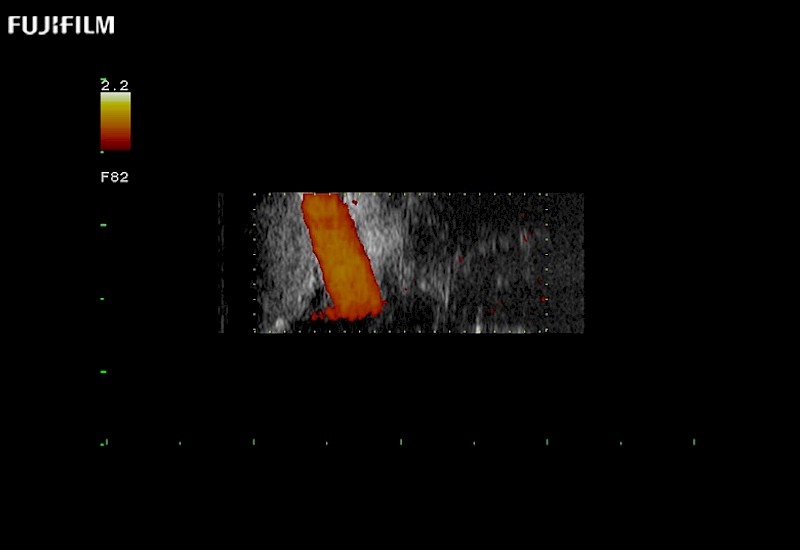

Exclusive 10mm side‐fire linear array transducer with 2.87mm diameter is ideal for real‐time visualization through and behind structures and instant, scalable definition of anatomy and vascularity including the ability to delineate and define tumor margins.

Main Specifications: